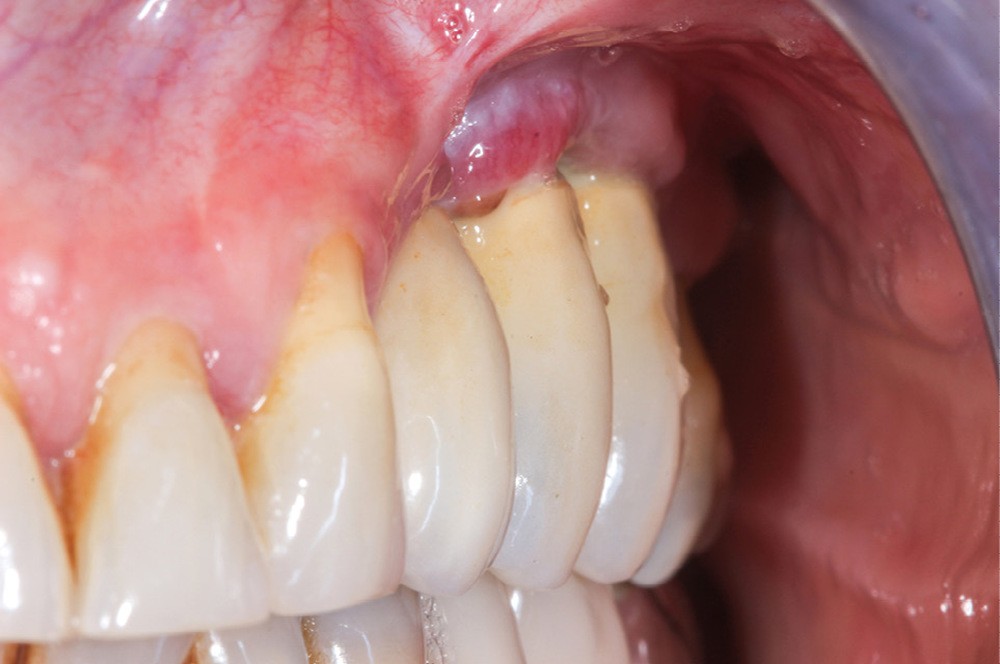

Le mode d’assemblage (prothèse vissée ou scellée) retenu peut aussi influencer la survenue d’une péri-implantite, avec une corrélation importante entre survenue de péri-implantite et présence d’excès de ciment de scellement [13, 14]. Une connexion dent-implant (prothèse dento-implanto-portée) est à proscrire, car plus propice aux péri-implantites et échecs mécaniques (fig. 4 et 5) [15, 16].